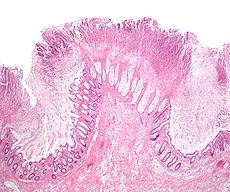

毒素A(TcdA)为肠毒素,可损伤肠道黏膜,诱发炎症反应,增加肠黏膜上皮通透性,肠道分泌大量液体,甚至出血性坏死。

毒素B(TcdB)为细胞毒素,破坏细胞骨架,直接损伤肠壁细胞,引发炎症反应而使肠道黏膜细胞变性、坏死、凋亡、脱落等。

艰难梭菌感染患者可以从无症状的细菌定植到腹泻(大于等于3次/天)并伴有发热、腹痛、腹胀、恶心和呕吐等全身性感染症状,重症患者可进一步发展成伪膜性肠炎、中毒性结肠、肠道穿孔、脓毒性休克,甚至死亡。